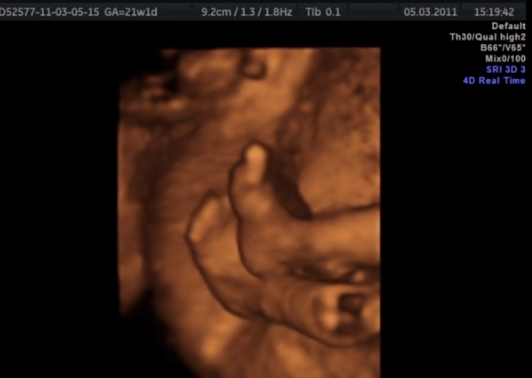

а мы 4D делали(не знаю почему но так называлось)) ни сколько не жалею) видео есть,сама скриншоты сделала))) ножечек, ручек)) мордахи)) и распеччатала в альбом)) конечно не похож абсолютно на родившегося в итоге))) но как он там капошился)) ногу на ногу складывал, целое кино))) и конечно видно отчетливо личико и носик и губки - все все все)) цвет просто только такой, оранжево-коричневый, цветных пока не сделали к сожалению) а в утробе все на монстриков похожи,9 месяцев в воде, опухшие))) хотя мне не показалось совсем)

На двухмерном узи человечек как человечек, а вот на 3D какие-то непонятные пузыри, размазано все и общая картина некрасивая получается)